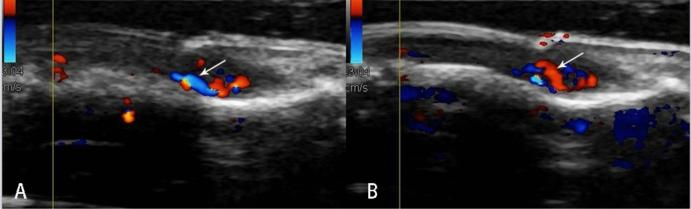

To evaluate the imaging features of subungual glomus tumors using 18 MHz high-frequency ultrasound with CDFI (Color Doppler Flow Imaging). 20 patients treated by surgical resection and examined by ultrasound between January 2008 and December 2019. All eligible cases are divided into two groups: Group A used the probe frequency of 9-14 MHz from January 2008 to December 2014, and Group B used the probe frequency of 18 MHz from January 2015 to December 2019. Patient demographics, clinical records, pathologic specimens and sonography features were reviewed. 50% of tumors in Group A and 100% of tumors in Group B showed clear boundary and regular shape. Blood flow signals were identified inside 50% tumors in Group A (3 in 6), all 14 cases with blood flow signals detected in Group B (14 in 14,100%). 2 cases were misdiagnosed and 1 case escaped diagnosis in Group A, no case was misdiagnosed in Group B. The accuracy of diagnosis rate of Group B is significantly higher than that of Group A. 18-MHz ultrasound combined with CDFI may be a practical useful tool for detecting subungual glomus tumors. More importantly 18-MHz ultrasound can obviously improve the diagnostic accuracy.

采用 18MHz 高频超声联合 CDFI(彩色多普勒血流成像)评估甲下血管球瘤的影像学特征。20 例患者经手术切除治疗,于 2008 年 1 月至 2019 年 12 月接受超声检查。所有符合条件的病例分为两组:A 组采用 2008 年 1 月至 2014 年 12 月探头频率为 9-14MHz,B 组采用 2015 年 1 月至 2019 年 12 月探头频率为 18MHz。回顾患者的人口统计学资料、临床记录、病理标本和超声特征。A 组 50%的肿瘤边界清晰,形状规则,B 组 100%的肿瘤边界清晰,形状规则。A 组 50%(3/6)的肿瘤内可见血流信号,B 组 14 例(14/14,100%)均可见血流信号。A 组有 2 例误诊,1 例漏诊,B 组无一例误诊。B 组的诊断准确率明显高于 A 组。18MHz 超声联合 CDFI 可能是一种实用的检测甲下血管球瘤的方法。更重要的是,18MHz 超声可以明显提高诊断准确率。